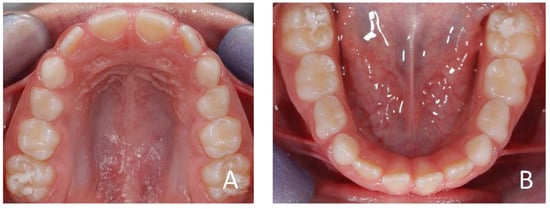

3.1. Clinical Case #1

3.2. Clinical Case #2

3.3. Clinical Case #3

3.4. Clinical Case #4